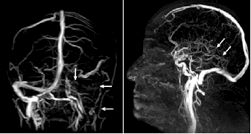

图2.左图示左静脉窦及颈静脉均无血流;

右图示深部静脉系统无血流(→)。